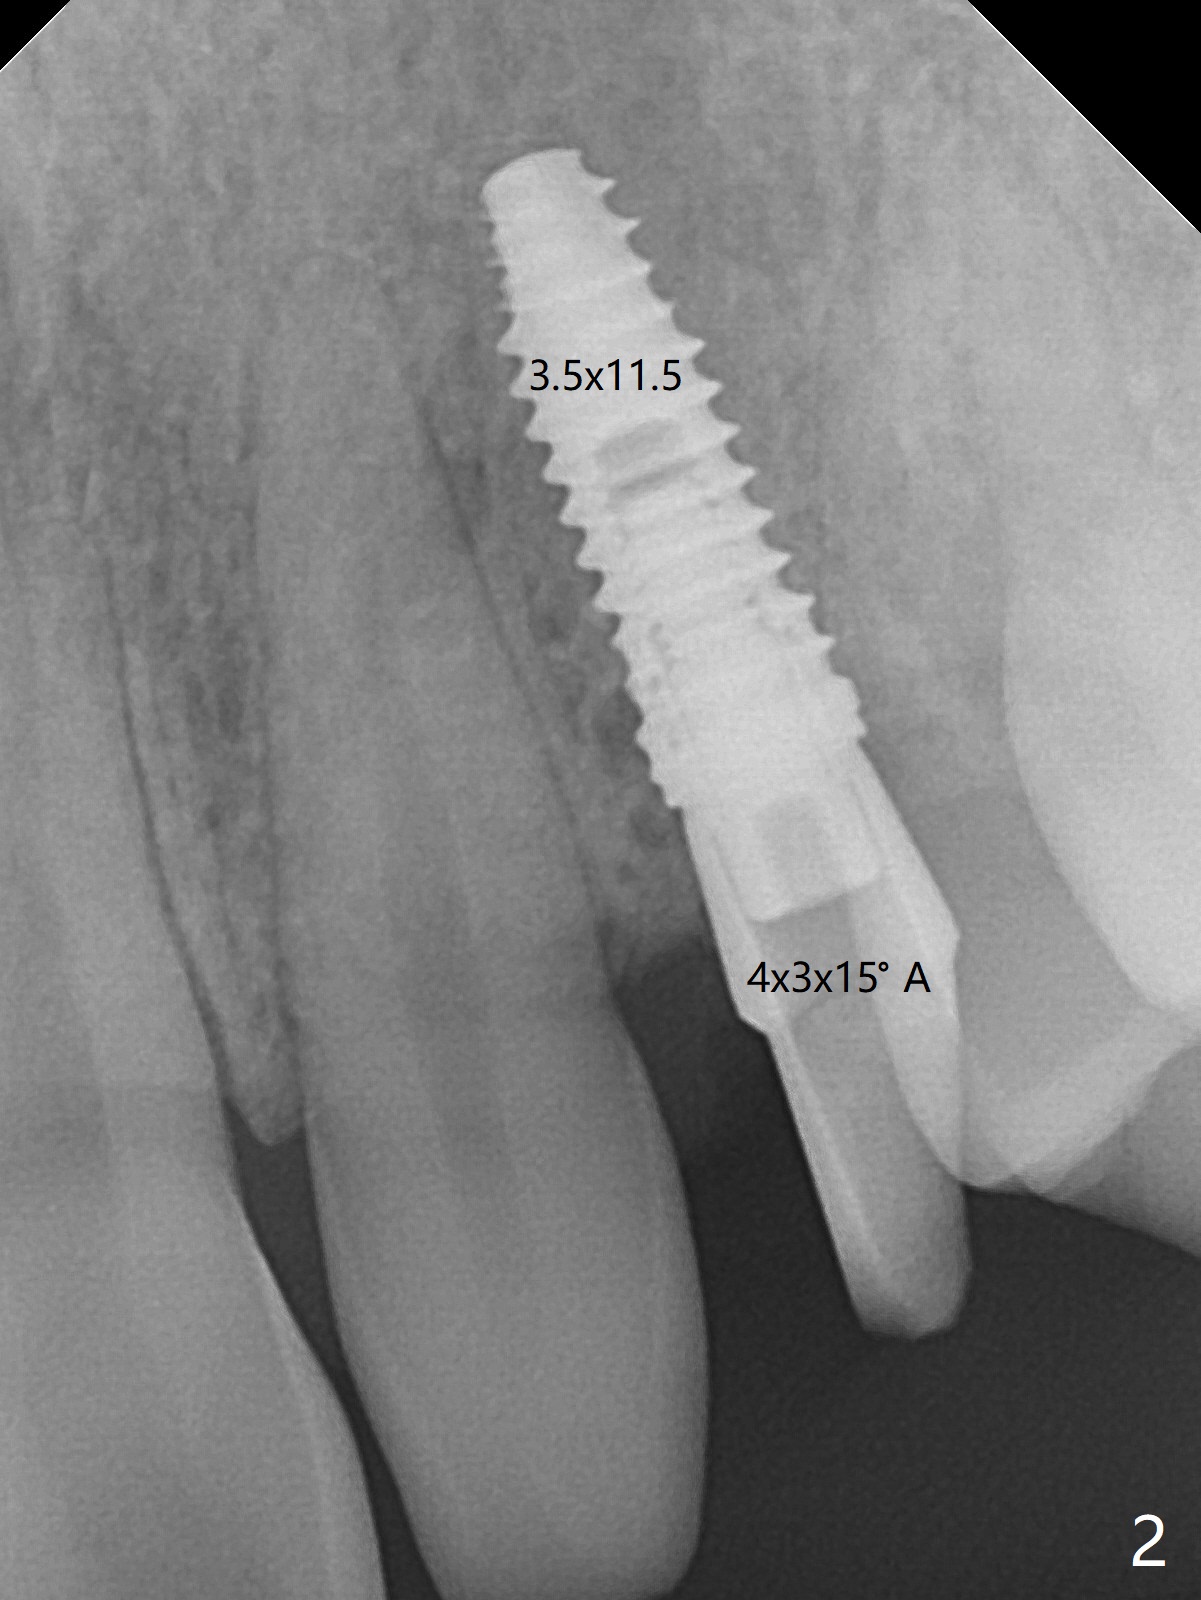

When the guide with 10.5 mm offset is seated at #11 after extraction, it looks buccal. Pointed drill creates an entry point in the mesial portion of the socket. PA, taken following 2.2x11.5 mm drill, shows acceptable mesiodistal trajectory (Fig.1). When a 3.5x11.5 mm implant is placed, it is difficult to withdraw the driver from the metal tube (Fig.1 *). There is no buccal gap with plenty of the lingual gap. A 4x3 mm x15 degree A-type angled abutment is placed (Fig.2). It appears that the dense palatal plate deviates the osteotomy and implant placement (as compared to the design, Fig.3). In fact osteotomy should have been prepared until 4 mm in diameter before increase in depth with 2.2 and 3 mm drills to eliminate buccal deviation. The ideal drill sequence would be point drill, 2.2x8.5 mm drill, 3x8.5, 3.5x8.5, 2.2x10, 2.2x11.5, PA to confirm trajectory, 3x10, 3x11.5 and 3x13. Torque associated with implant placement is pure, not derived from friction between the driver and the metal tube. There is mesial crestal bone loss 4 months postop (Fig.4, as compared to immediate postop in Fig.2 (*)). Crestal bone loss does not get worse between 4 and 6.5 months postop (Fig.4,5). The bone density increases 8 months post cementation (Fig.6).